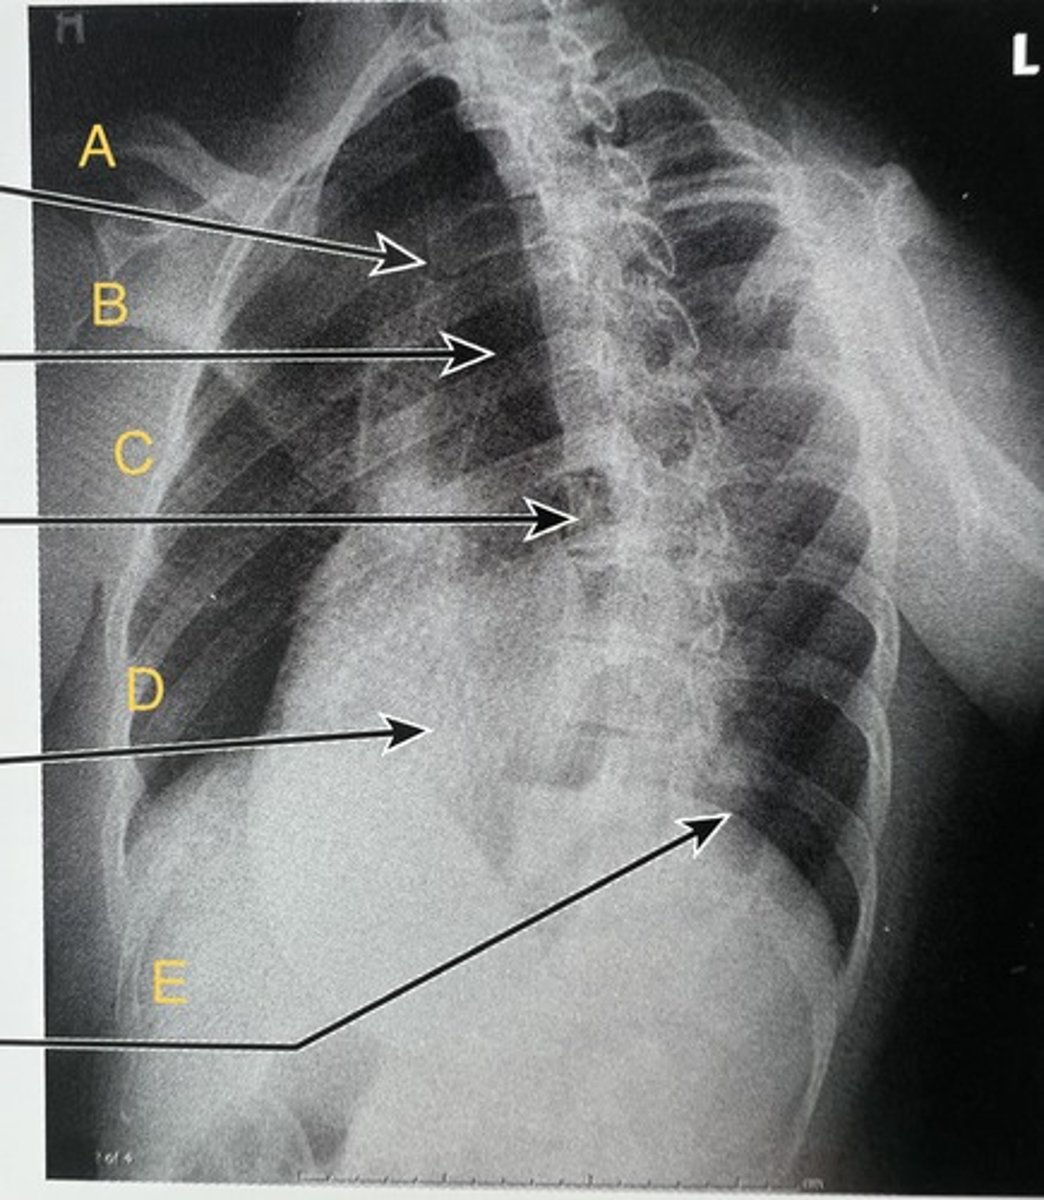

L 1st rib

A.

L clavicle

B.

T8 body

C.

T9 L posterior rib.

D.

T12 body

E.

AP T-spine

What position?